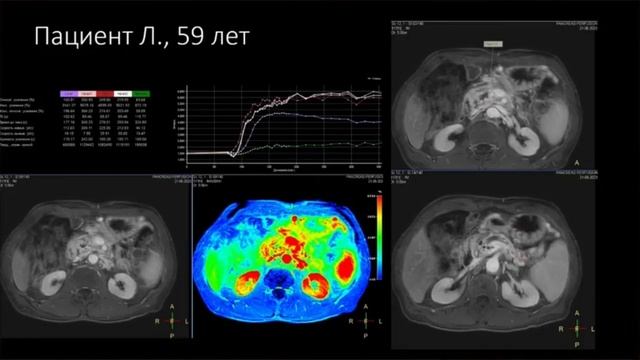

Мр перфузия

Мр перфузия 119 фотографий